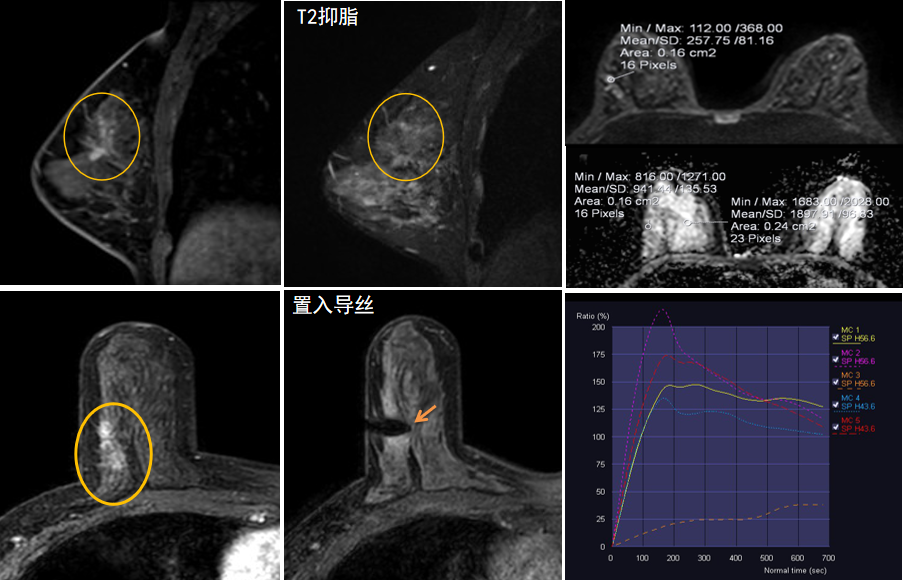

今年45歲的某女士,兩個(gè)月前行超聲檢查發(fā)現(xiàn)右乳結(jié)節(jié),乳腺X線(xiàn)攝影檢查提示右乳外上象限局部腺體結(jié)構(gòu)扭曲并簇狀無(wú)定形鈣化,為了進(jìn)一步評(píng)估病變性質(zhì)并確定范圍進(jìn)行了乳腺M(fèi)R平掃 DWI 增強(qiáng)的檢查,經(jīng)MR評(píng)估發(fā)現(xiàn)右乳病變范圍較廣,評(píng)估為BI-RADS 4類(lèi)可疑病變,需要取得病理學(xué)結(jié)果。

只能借助影像學(xué)引導(dǎo),但超聲僅顯示了病變中的小結(jié)節(jié),X線(xiàn)攝影(鉬靶)顯示的病變邊界比較模糊,要想做到精準(zhǔn)完整切除必須借助MR的引導(dǎo),而這一技術(shù)對(duì)軟硬件平臺(tái)及人員技術(shù)都有很高的要求,因此,多年來(lái)一直是我國(guó)乳腺病變?cè)\療的盲區(qū),經(jīng)常是MR發(fā)現(xiàn)可疑病變但卻無(wú)法處理。目前全國(guó)僅有少數(shù)幾家醫(yī)院開(kāi)展了這方面的部分工作。

西安國(guó)際醫(yī)學(xué)中心醫(yī)院影像診療中心陳寶瑩主任團(tuán)隊(duì)有著十余年影像引導(dǎo)下乳腺介入診療的經(jīng)驗(yàn),借助醫(yī)院高精尖的MR平臺(tái),成為西北首個(gè)全面展開(kāi)MR引導(dǎo)下各項(xiàng)乳腺介入診療技術(shù)的團(tuán)隊(duì),能夠?qū)Τ暭叭橄賆線(xiàn)無(wú)法顯示或顯示不清的病變進(jìn)行MR引導(dǎo)下的導(dǎo)絲定位、穿刺活檢及真空輔助旋切。

陳寶瑩主任及其帶領(lǐng)的MR介入診療小組詳細(xì)詢(xún)問(wèn)了病情,分析了患者資料,并與患者和臨床醫(yī)生進(jìn)行了充分溝通,確定于手術(shù)前為患者實(shí)施MR引導(dǎo)下的病變穿刺導(dǎo)絲定位和體表范圍確定。手術(shù)前陳寶瑩主任帶領(lǐng)聶品醫(yī)師、馬小偉技師、韓愛(ài)萍護(hù)士長(zhǎng)等MR介入診療小組成員,借助MR高清的圖像顯示和定位系統(tǒng),確定病變范圍,精準(zhǔn)穿刺置入定位導(dǎo)絲,并準(zhǔn)確標(biāo)記出病變體表范圍,整個(gè)過(guò)程患者無(wú)任何不適。在定位導(dǎo)絲和體表范圍標(biāo)記的輔助下,甲乳外科劉曉敏主任精準(zhǔn)切除了病變,解除了患者的后顧之憂(yōu)。

國(guó)內(nèi)外指南均建議40歲以上的女性每年行一次雙乳X線(xiàn)攝影(鉬靶)檢查,以篩查乳腺癌。對(duì)于乳腺癌高危人群40歲以前即建議開(kāi)始乳腺癌篩查,除了進(jìn)行乳腺X線(xiàn)攝影(鉬靶)篩查外需要補(bǔ)充MR檢查,MR檢查敏感性最高,能夠發(fā)現(xiàn)大量X線(xiàn)攝影和超聲檢查陰性的可疑病變,基于多模態(tài)、多參數(shù)的結(jié)構(gòu)和功能成像的基礎(chǔ)上,MR能夠精準(zhǔn)顯示病變位置、范圍以及病變內(nèi)的活性區(qū)域,MR引導(dǎo)下的介入診療不但解決了僅在MR顯示的病變的處置難題,而且能夠精準(zhǔn)定位活性區(qū)域,保證了定位、活檢及旋切的準(zhǔn)確性。